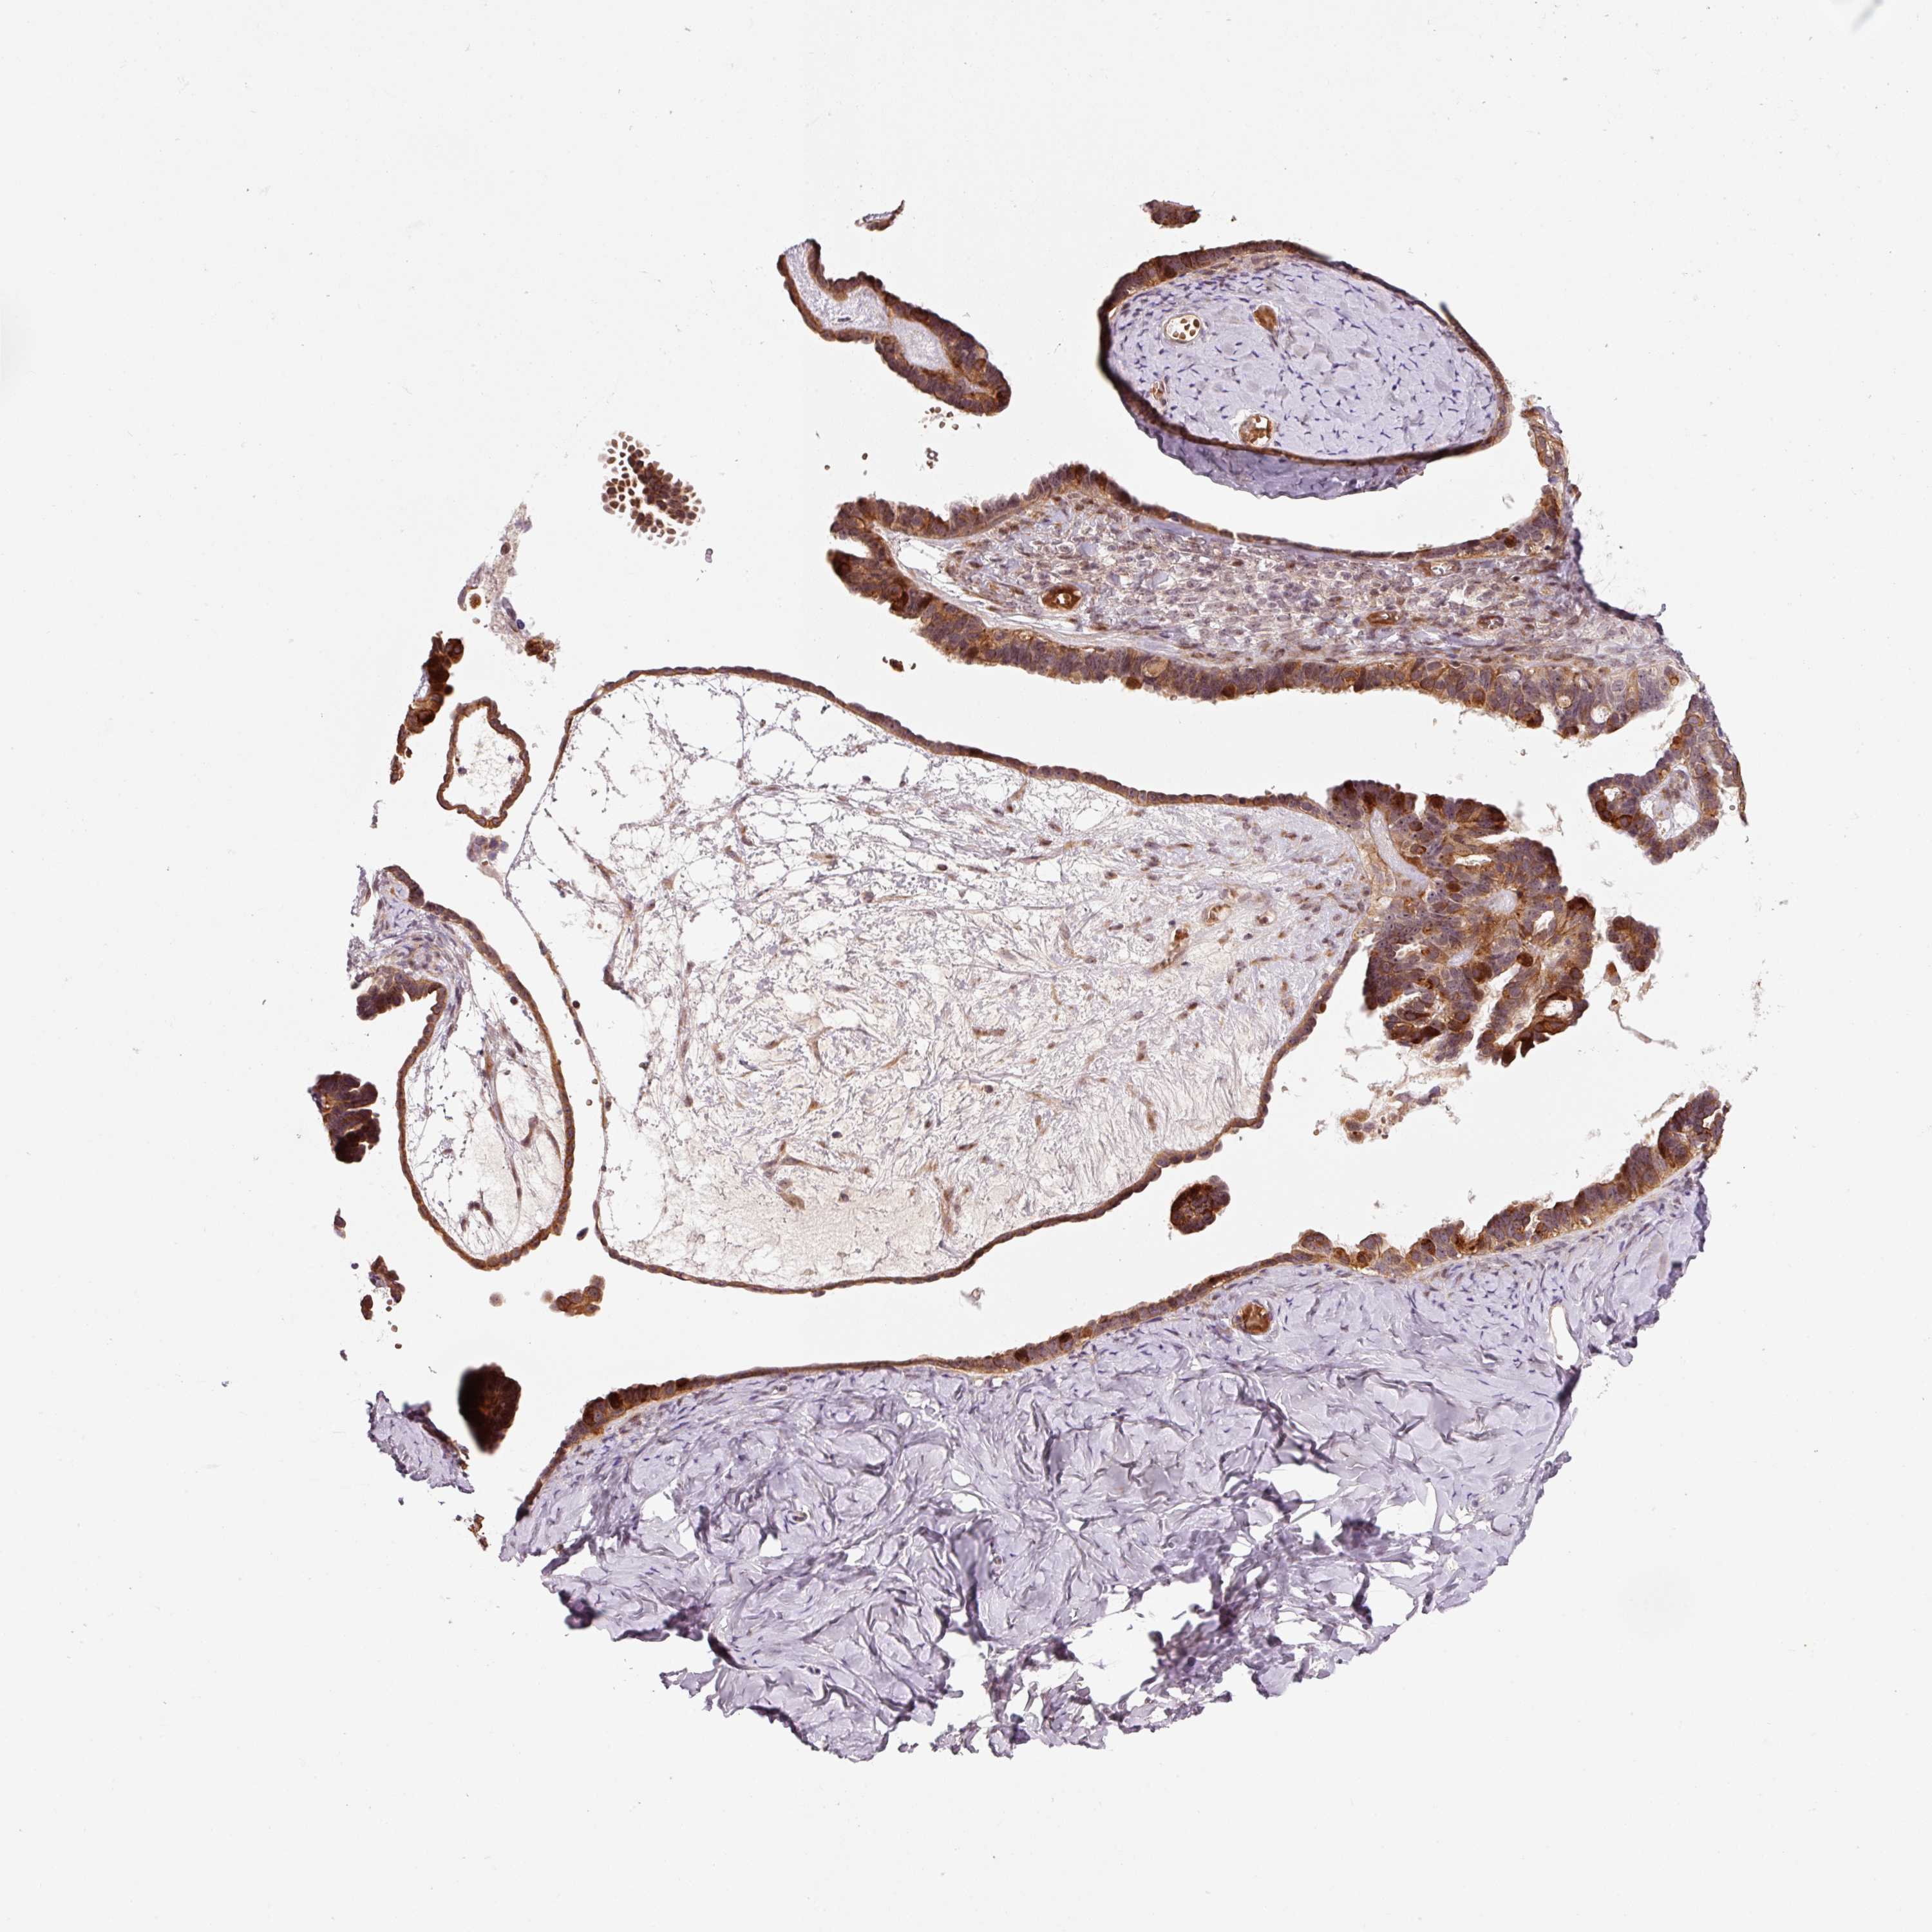

OVARIAN CANCER - Protein expressioni

A mouse-over function shows sample information and annotation data. Click on an image to view it in a full screen mode. Samples can be filtered based on level of antibody staining by selecting one or several of the following categories: high, medium, low and not detected. The assay and annotation is described here.

Note that samples used for immunohistochemistry by the Human Protein Atlas do not correspond to samples in the TCGA dataset.

Antibody stainingi

Antibody staining in the annotated cell types in the current human tissue is reported as not detected, low, medium, or high, based on conventional immunohistochemistry profiling in selected tissues. This score is based on the combination of the staining intensity and fraction of stained cells.

Each image is clickable and will lead to virtual microscopy that enables deeper exploration of all samples and also displays staining intensity scores, fraction scores and subcellular localization as well as patient and tissue information for each sample.

Adenocarcinoma, NOS